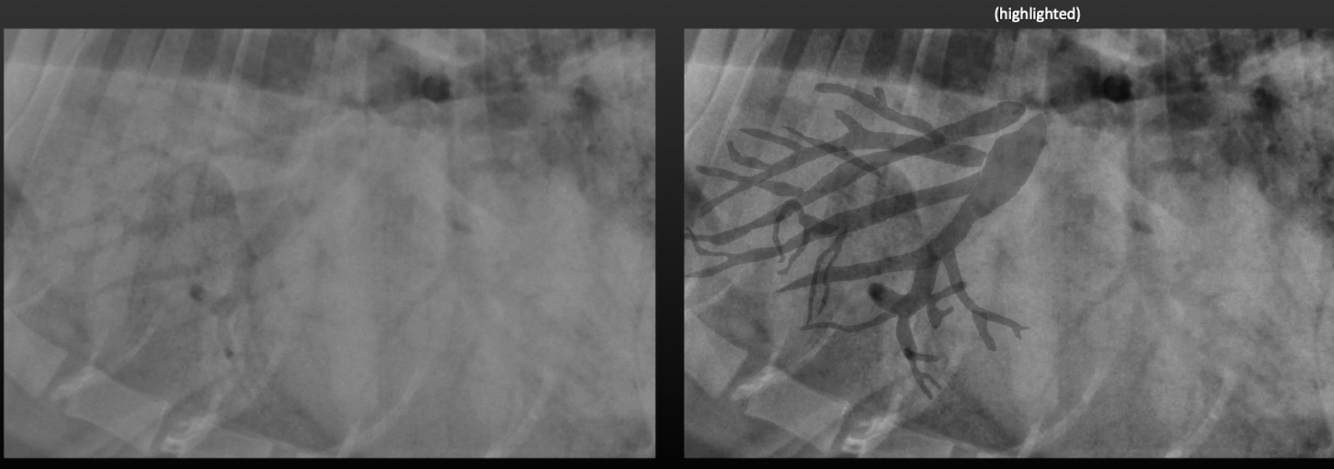

Lung Pattern? Where is the hilus?

Alveolar

Air bronchogram

Lung Pattern?